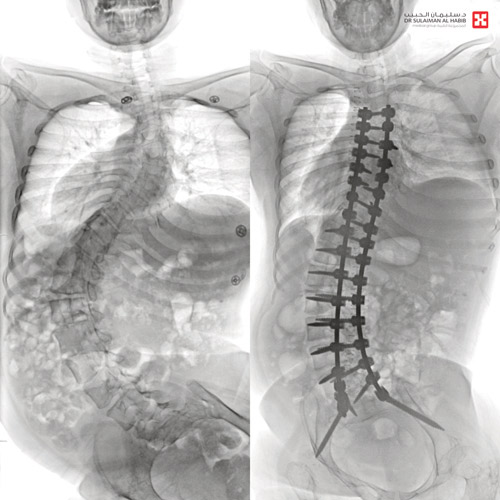

وأجرى لها الفريق الطبي، مجموعة من الفحوصات الطبية الدقيقة، التي بينت إصابتها بحالة انحراف «جنف صدري» بدرجة 65 للفقرات الصدرية وجنف قطني بدرجة 55 ودرس الفريق الطبي الحالة على ضوء نتائج الفحوصات والتحاليل، وخلص إلى ضرورة التدخل الجراحي لعلاج العيوب، والحد من المضاعفات، وبعد اتخاذ كافة التدابير الطبية لمثل هذه الحالات المعقدة، أخضعت السيدة لعملية جراحية استغرقت 4 ساعات تم فيها تقويم العمود الفقري بعدد 23 من البراغي والقضبان المعدنية من التايتانيوم والكوبالت كروم والطعوم العظمية الصناعية وتثبيت ودمج الفقرات، وشارك في العملية التي استمرت 4 ساعات، فريق طبي استخدم في العملية مجموعة من أحدث الأجهزة الطبية، التي ساهمت مع الكوادر الطبية عالية الكفاءة والتأهيل بالمستشفى في إنجاحها، ونقلت المريضة إلى جناح التنويم بعد العملية، حيث بدأت في التحسن بشكل متسارع بعد خروجها من غرفة العمليات، إذ استطاعت الوقوف والمشي خلال 24 ساعة، مع فريق العلاج الطبيعي المتمرس، كما أن طولها مع النجاح الكبير للتعديل زاد نحو 3 سم، وخرجت من المستشفى وهي بصحة جيدة، وتوقع أن تستعيد كامل عافيتها سريعاً، مع الالتزام بالبرنامج العلاجي المصمم لها وبإرشادات الفريق الطبي المعالج، مشيراً إلى أن مثل هذه الحالات تسترجع القدرة على الحركة الطبيعية، خلال ستة أشهر من العملية وإمكانية الحمل والولادة الطبيعيتين بعد سنة بمشيئة الله تعالى.